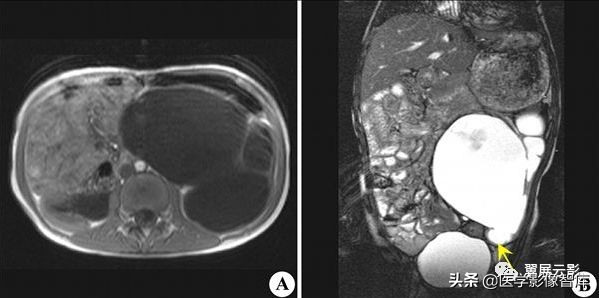

肾上腺转移瘤

肾上腺由于血供丰富,转移瘤很常见,在血行性转移的好发部位中占第四位,肾上腺转移瘤常见的原发性肿瘤是肺癌,乳腺癌,其次是胃癌,肝癌,胰腺癌,甲状腺癌,肾癌以及黑色素瘤与淋巴瘤,肾上腺转移瘤通常很少影响肾上腺功能,因而不见其本身内分泌症状;仅有很少肾上腺转移瘤产生肾上腺素分泌减少的表现。

右侧肾上腺小腺瘤

应该注意描述肾上腺转移瘤的特点,肿瘤一般为双侧性,边缘较不规则,由于肿瘤出血坏死,信号较不均匀,T2WI信号较高,动态增强扫描转移瘤一般强化明显且持续较长时间,注意询问病史,确定原发灶。邻近其他脏器的转移性病灶和腹膜后肿大淋巴结也应观察描述。